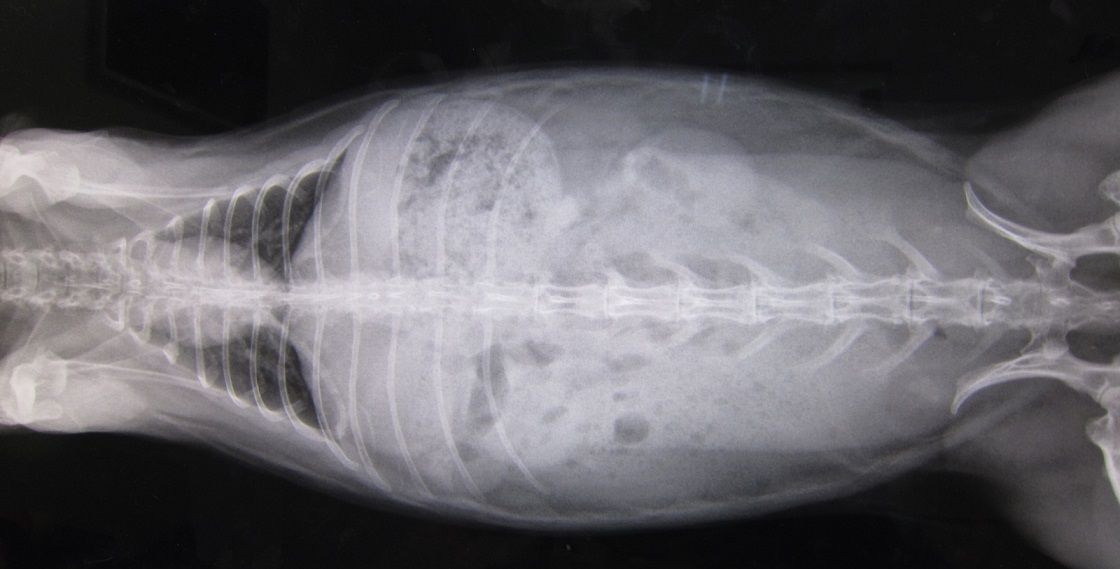

kagu0812

無いんちゃう?」

kagu0813

「な 先生、無いやんね無いやんね

というか、かぐらさんお腹周りが大きいなと思ってたら

脂肪も多いです…(。--)ノ (上下外側の色の薄い部分…)

ただ、強いてこじつけレベルで指摘するとしたら…こうゆう白い塊ね。

kagu0811

これは左右対象にあるから恐らく乳頭と思われる… それと、

kagu0810

…印付けに自信がないですが、薄いおはじきのような白色は写ってます。

上にいくと消化器官ですが、丸くなる手前かも、とかとか…

…ちょっとモヤっと感は残るんですが、

「喜んでも良いと思います」て言うてたから、喜んでいいんやと思います(^-^;)